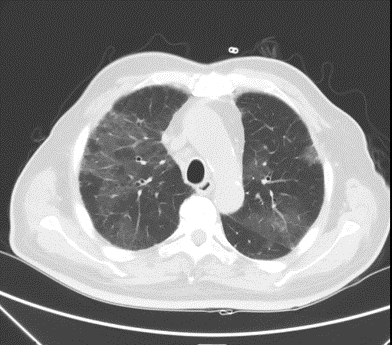

元旦过后,节日的欢乐气氛还未散去,洪叔(化名)一家却是愁肠百结,仍沉浸在忧虑之中。洪叔因持续的喘息和呼吸困难,已在两家医院间辗转。他的病情日益严重,某医院的胸部CT显示他的双肺已近乎“白肺”,这无疑给他的治疗带来了极大的挑战。面对这样的困境,洪叔一家毅然决定转至我院寻求希望。

明确了治疗方向后,医护人员迅速展开了有条不紊的救治工作。既然有两个问题需要同时处理,那么救治方案必须“双管齐下”,全面而细致。经过积极的抗真菌、抗炎治疗以及改善心功能等措施,洪叔的血氧状况很快得到了改善,从经鼻高流量吸氧逐渐过渡到鼻导管吸氧,活动耐量也逐步恢复。复查胸部CT显示,病变部分有了明显的改善。

胸部CT对比:治疗前(左),治疗后(右)